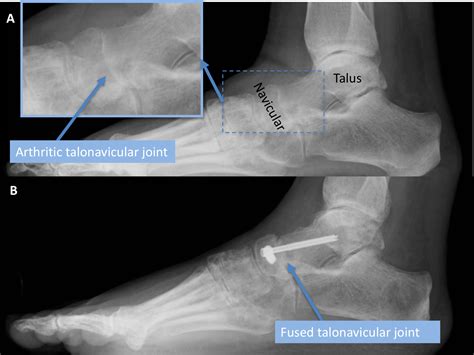

The primary goal of fusing ankle bones is to alleviate pain by stopping the grinding of damaged cartilage surfaces within the ankle joint. Over time, wear and tear, trauma, or underlying conditions like rheumatoid arthritis can cause the protective cartilage to deteriorate, leading to bone-on-bone contact. During the procedure, the surgeon removes the remaining damaged cartilage from the joint surfaces and secures the bones together using hardware like metal screws, plates, or rods. Over several months, the body’s natural healing process bridges these bones with new bone tissue, creating a solid, permanent unit.

While the prospect of losing motion in a joint may seem daunting, the outcomes for patients with end-stage arthritis are often transformative. By eliminating the source of friction and inflammation, patients frequently experience a drastic reduction in pain, allowing them to walk, work, and move with greater comfort than they have felt in years.